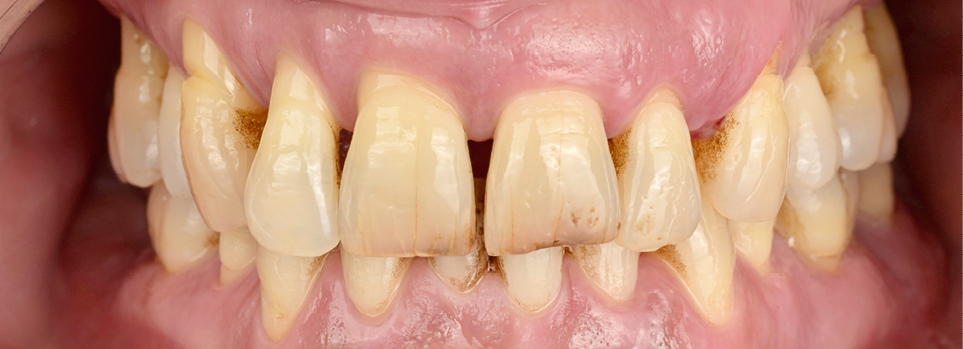

Avant toute intervention chirurgicale, un assainissement parodontal a été effectué. Les deux arcades ont été traitées afin de stabiliser l’environnement biologique (fig. 1). L’analyse complète du volume osseux et gingival a donc été réalisée à partir d’une situation clinique compatible avec une prise en charge implantaire ; un parodonte sain réduit (fig. 2).